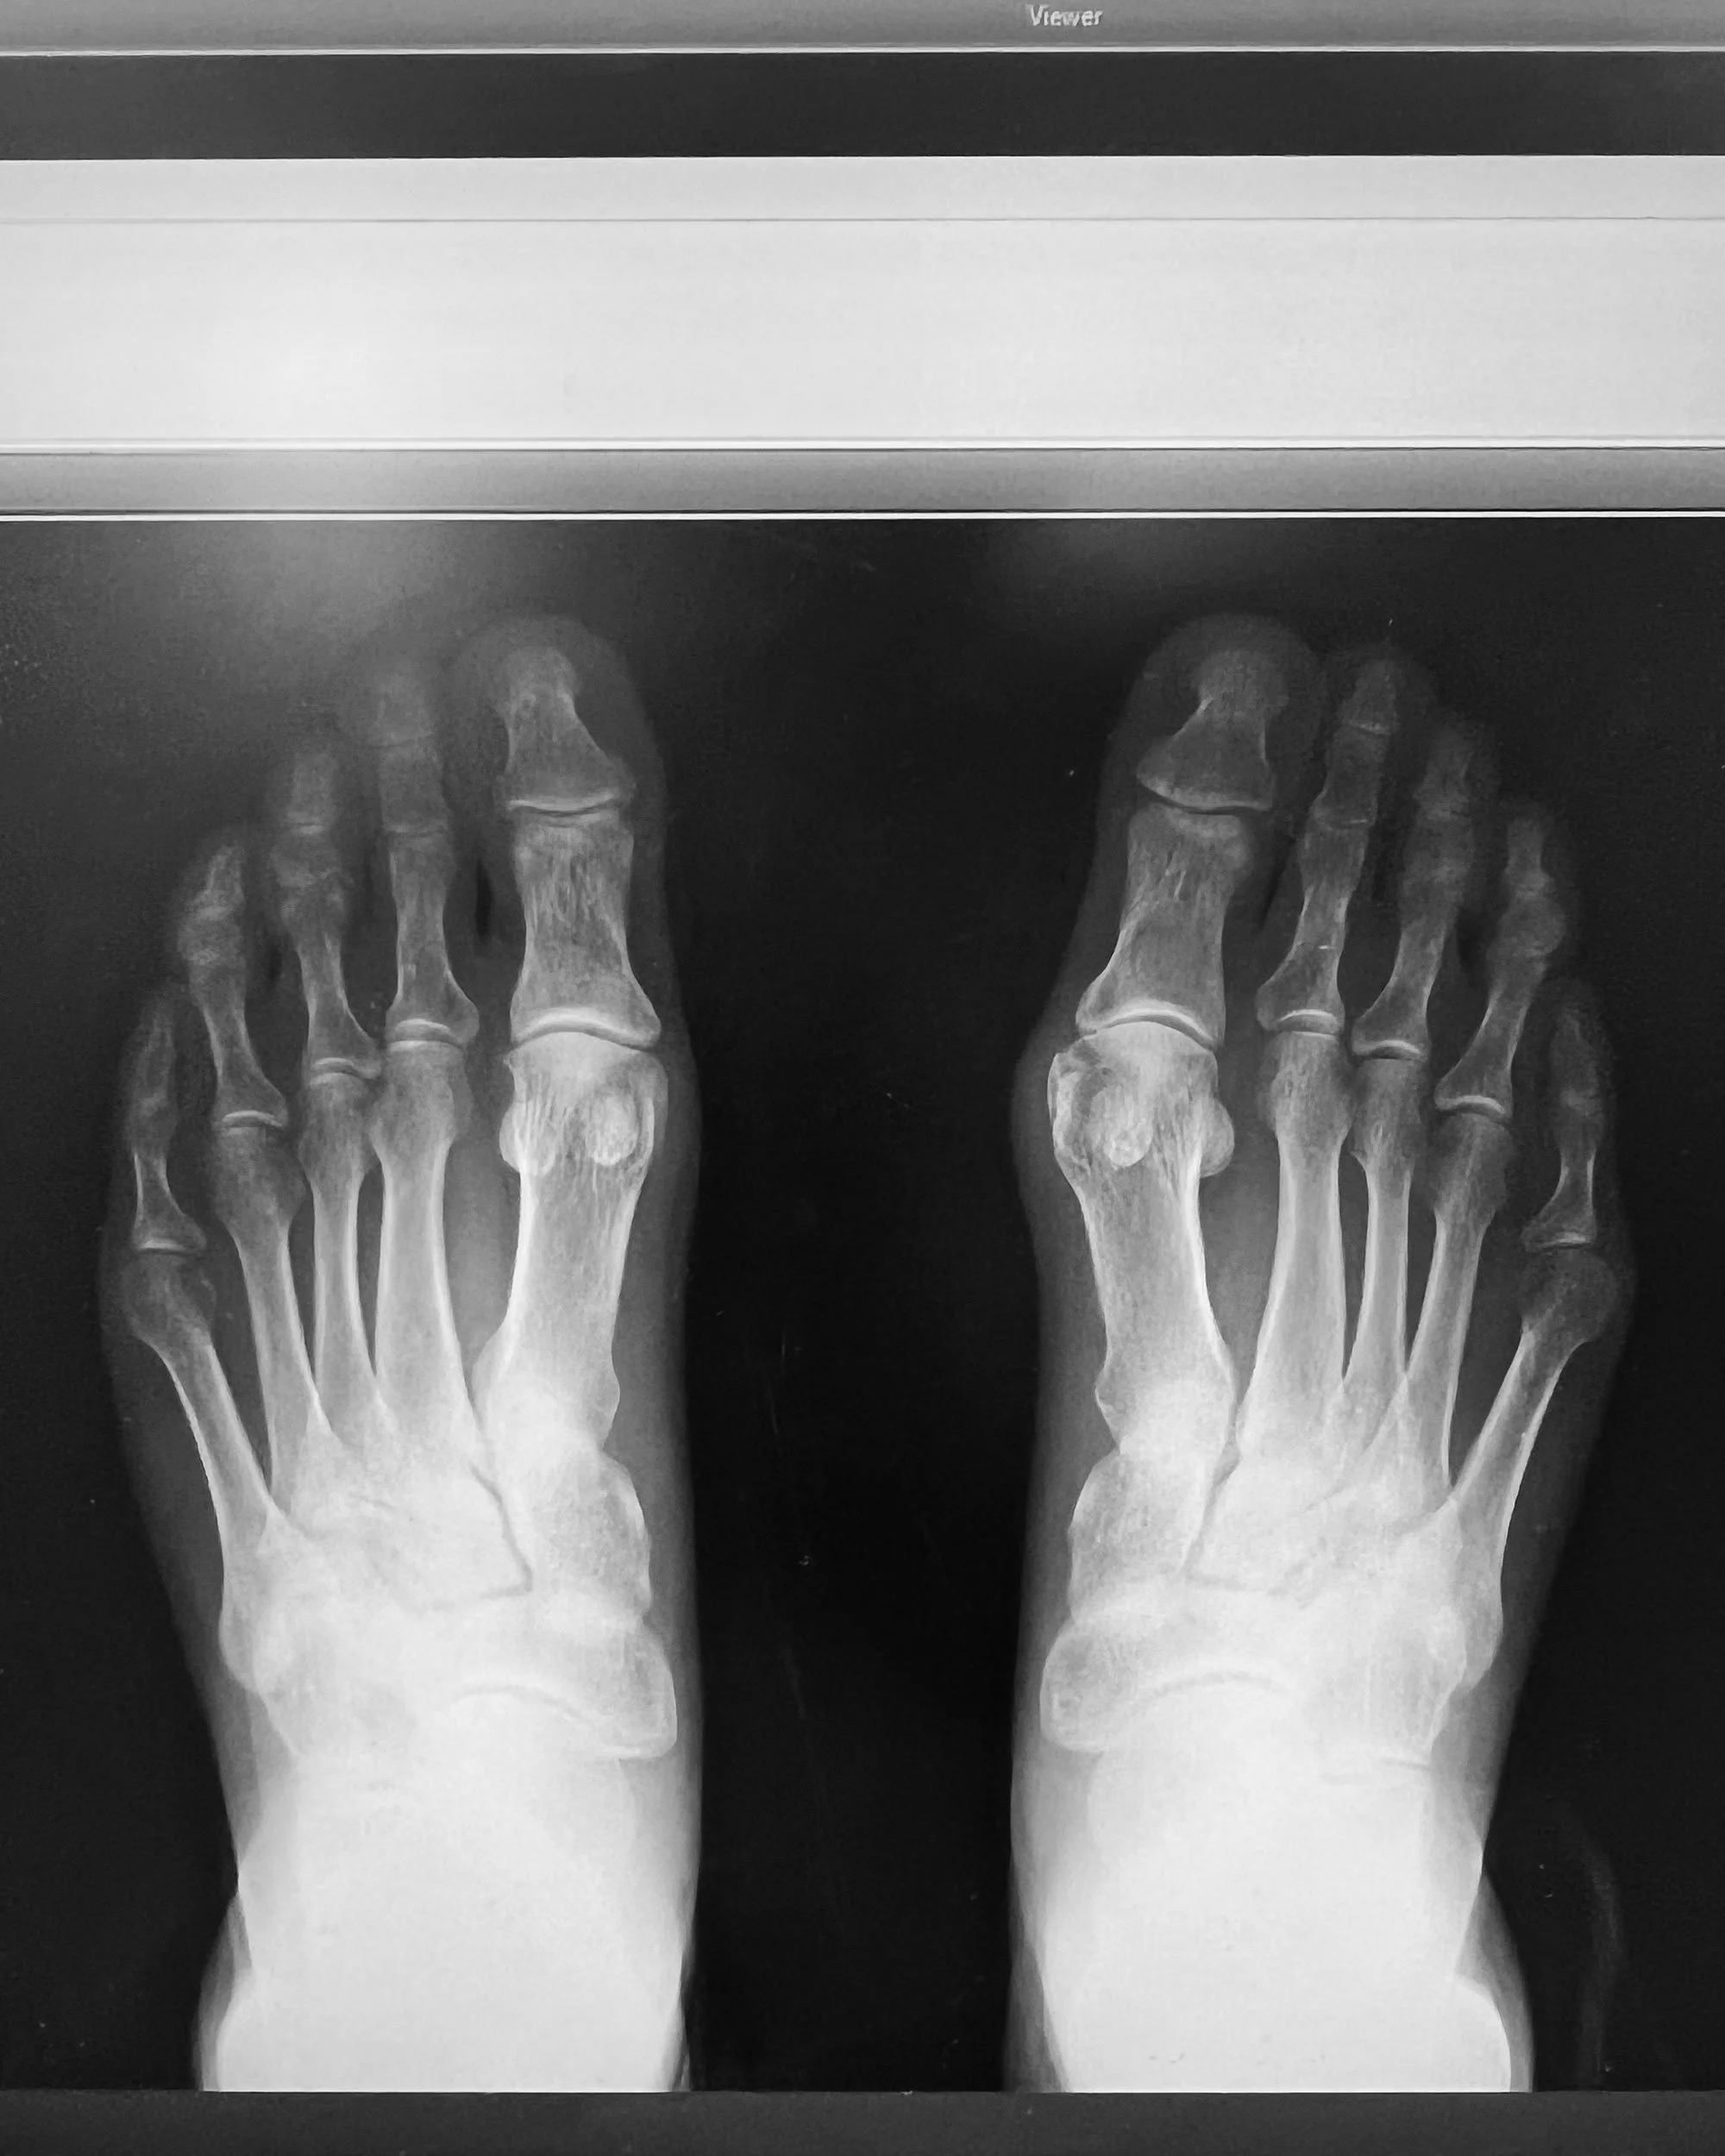

Pharmacal